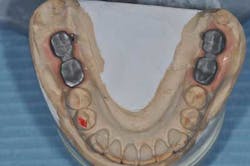

Figs. 5a and b: Impression for the RPD framework including the PFM frameworks and mounting

- Try-in and final bite registration.

Figs. 6 a, b, c, and d: RPD framework try-in, bite record with mandibular implant-supported metal frameworks and mounting